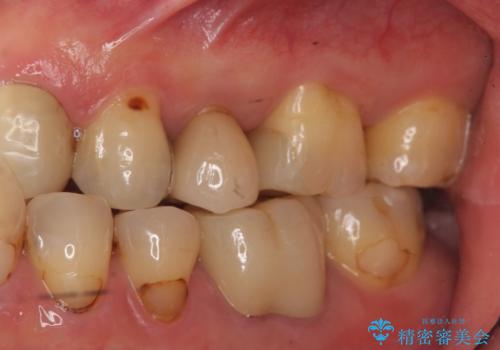

②ジルコニアクラウンで被せる

表面の黒いところまで覆う事ができる。

ただし、①よりも歯を大きく削ることになる。

患者様と相談し、黒いところも目立たなくしたいとのご希望だった。

そのため、歯質の削除量は増えるが、クラウンで被せる②の方針で行うことになった。

- 仮歯・ジルコニアクラウン 12.1万円 費用は治療当時の料金となります

白い被せ物が入り希望に沿った処置となり

大変満足して頂けました。